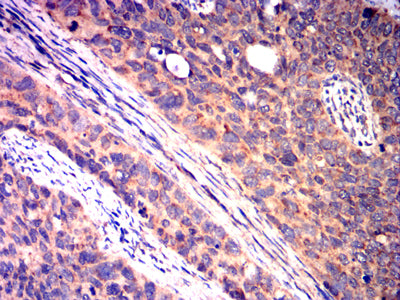

Immunohistochemical analysis of paraffin-embedded human cervical cancer tissues using CD40 mouse mAb with DAB staining.